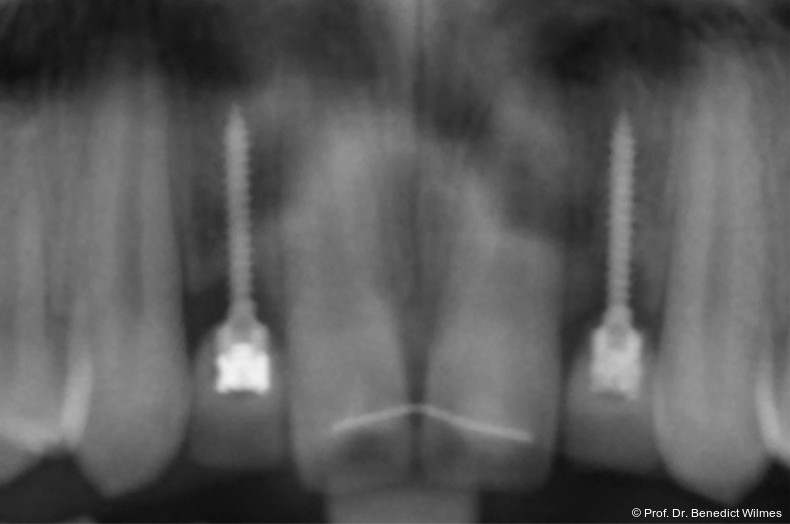

Bei einer elfjährigen Patientin fehlten bei Zustand nach Frontzahntrauma im Alter von neun Jahren beide oberen mittleren Schneidezähne (Abb. 8a+b). Als temporärer Ersatz wurden Miniimplantate (Abb. 9, 2 x 13 mm) eingesetzt und Kronen im Labor angefertigt, welche auf den Miniimplantaten verschraubt wurden (Abb. 10a+b). Die Miniimplantate wurden im Alter von 19 Jahren, also nach achtjähriger Nutzung (Abb. 11a+b), durch dentale Implantate ersetzt.